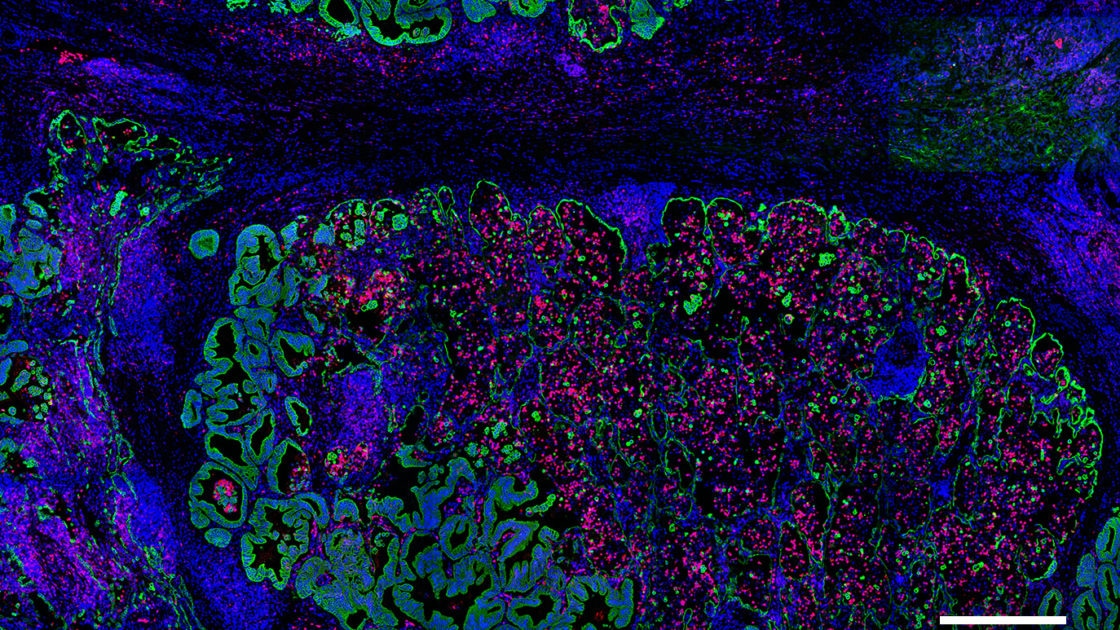

Morphology markers are biological molecules identified as reliable probes for histological techniques such as immunohistochemistry (IHC) and in situ hybridization (ISH) that allow for microscopic visualization of tissue structures. Most commonly, fluorescently labeled antibodies and oligonucleotides are used as visualization probes to identify the anatomical structures, cell types, and tissue compartments present in each section of interest. Specific landmarks chosen as targets to probe, or mark, orient the observer to the tissue morphology for selecting and segmenting regions of interest (ROIs) for high-plex spatial multiomics of FFPE and fresh frozen tissue sections such as that done with the GeoMx® Digital Spatial Profiler.